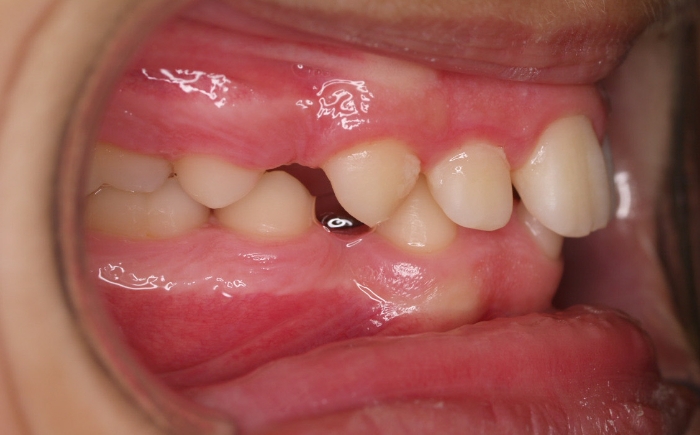

El paciente M.C. acude a nuestra consulta por:

– Apiñamiento importante

– Perfil convexo

– Forma arcada estrecha

-sobremordida

Fotos antes tratamiento: